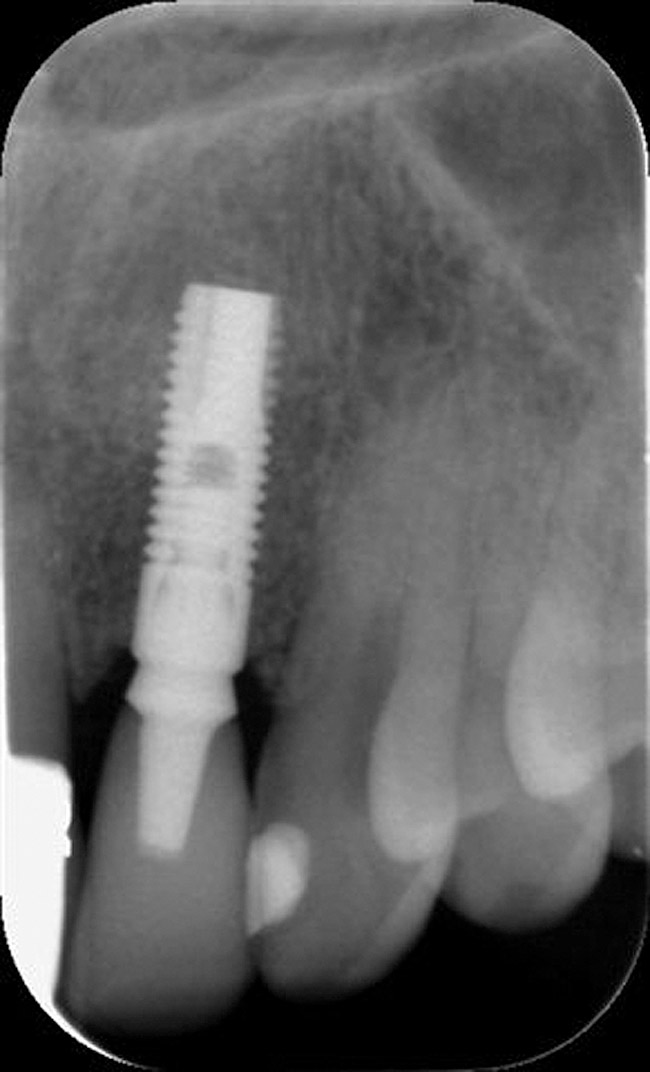

Figure 2 Identification of sufficient inter-radicular space: The radiographic representation of inter-radicular space (Fig 2) reveals abundant space for a single-tooth implant; at the alveolar crest,

> 6 mm of interproximal space is available for placeme

Figure 2

Figure 3 Identification of sufficient inter-radicular space: The radiographic representation of inter-radicular space (Fig 2) reveals abundant space for a single-tooth implant; at the alveolar crest,

Figure 3

The typical minimal mesiodistal dimension that may be considered for simple single-tooth replacement of an anterior tooth is 6 mm. This may not seem to be an impediment to implant placement; however, several common anatomic situations are often encountered. While the typical dimension of a lateral incisor is greater than 6 mm in the mesiodistal dimension, teeth are often lost without immediate placement, and the bound edentulous space may be reduced. Natural tooth crowding with rotation may result in less than 6 mm of mesiodistal dimension. Another concern is proximal root convergence leading to less than 6 mm of space for implant placement despite the dimension available for the crown. Finally, lateral incisor agenesis that is treated by orthodontics may not always provide 6 mm of space for implant placement or may result in proximal root convergence. There must exist 6 mm of mesiodistal bone dimension between adjacent teeth to permit an implant (> 3.5 mm in diameter) to be placed with greater than 1 mm of bone at mesial and distal interproximal locations (Figure 2 and Figure 3). The advent of narrow implants (eg, 3 mm) provides a new opportunity to address smaller (approximately 5 mm) mesiodistal dimensions.

Additional attention must be paid to the osseous architecture related to the adjacent teeth, as this controls interproximal tissue form.7 The crest of healthy bone is 4.5 mm to 5 mm from the contact point between anterior teeth8; a similar 5-mm distance from the contact point to the bone crest has been measured between an implant and natural tooth. An important and additional rule to guide esthetic implant outcomes is that the adjacent tooth should possess interproximal bone levels no further than 6 mm from the natural tooth contact point (Figure 4 through Figure 6). While the ideal distance is justifiably indicated to be 5 mm, this 6-mm rule establishes a point at which marked interproximal tissue deficiencies and asymmetry will not be overcome.